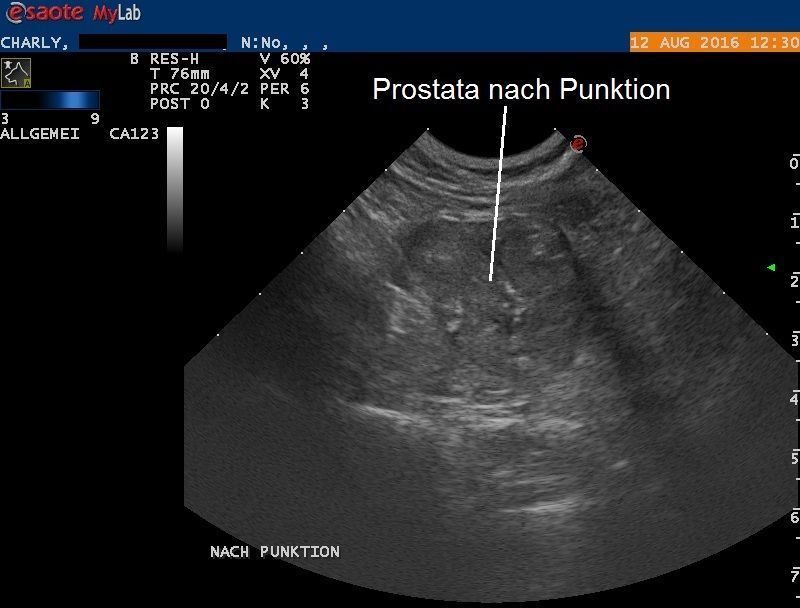

In einem zweiten Untersuchungsschritt werden die Prostata und die vergrösserten Lymphknoten unter leichter Narkose unter Ultraschallführung punktiert: Die Prostatapunktion liefert etwa einen Milliliter einer bräunlich-roten, schleimigen, stark riechenden gallertigen Flüssigkeit. Nach der Punktion ist zu erkennen, dass die zuvor festgestellte Flüssigkeit in der Prostata komplett entfernt worden ist.